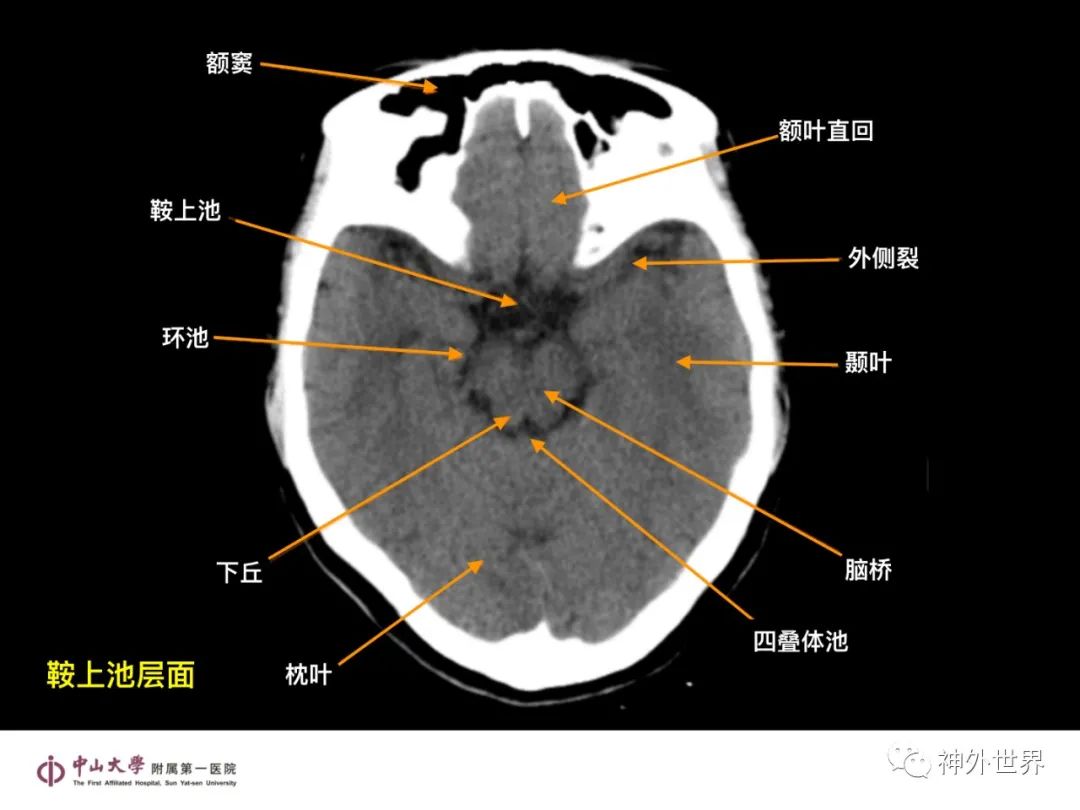

大脑MR、CT 的阅片技巧,超赞 !